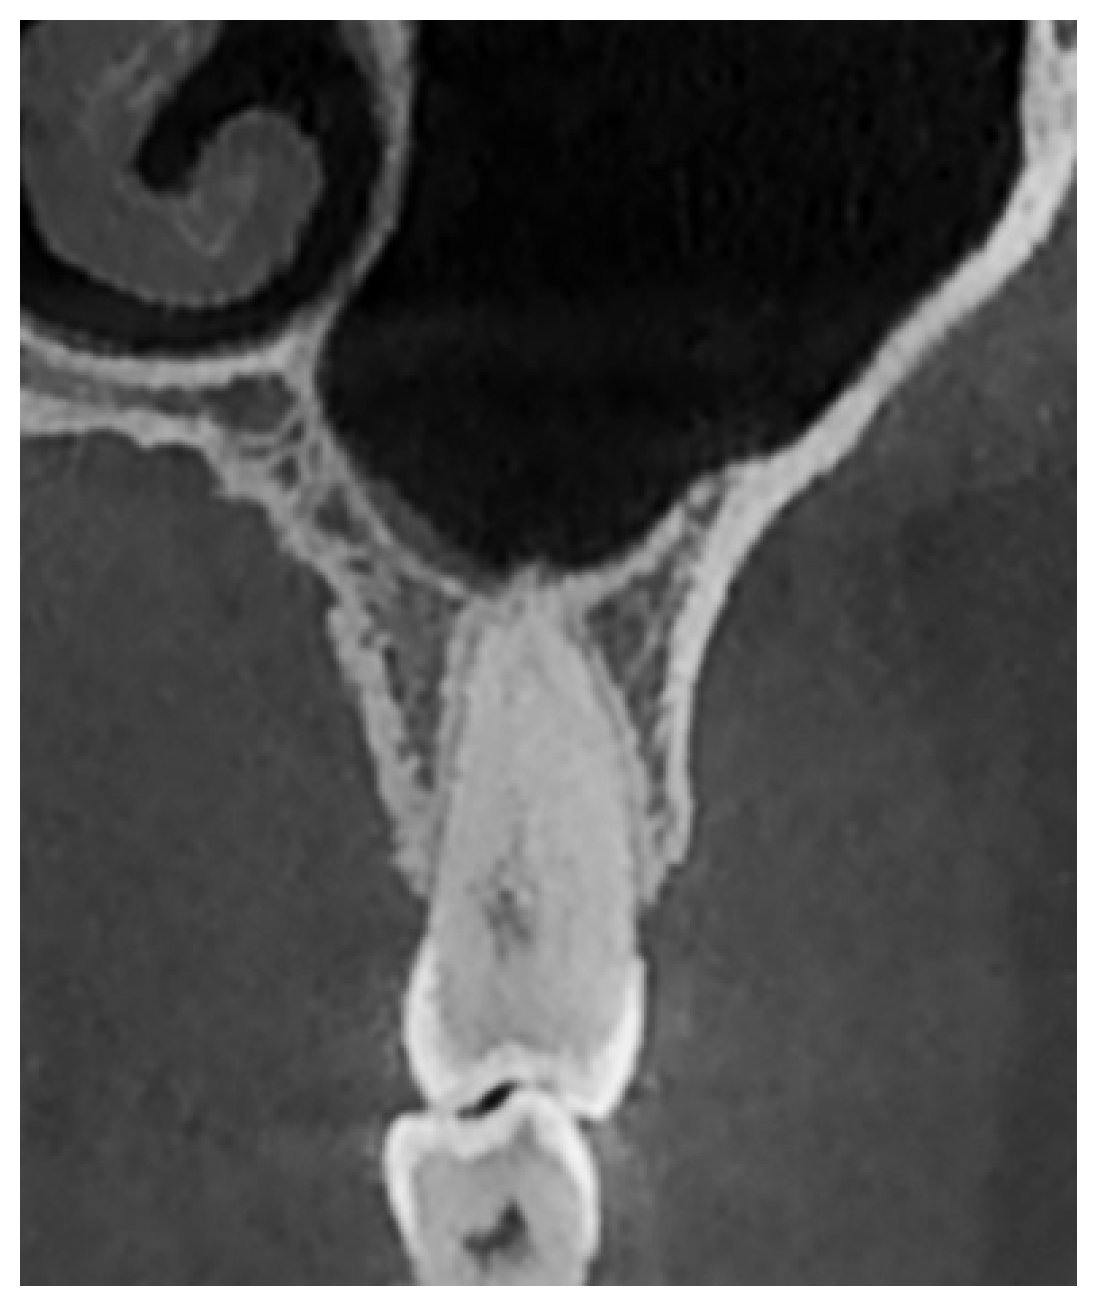

- Type II: Tangential relationship—the tooth root is located 0–0.20 mm from the sinus floor (Figure 3).